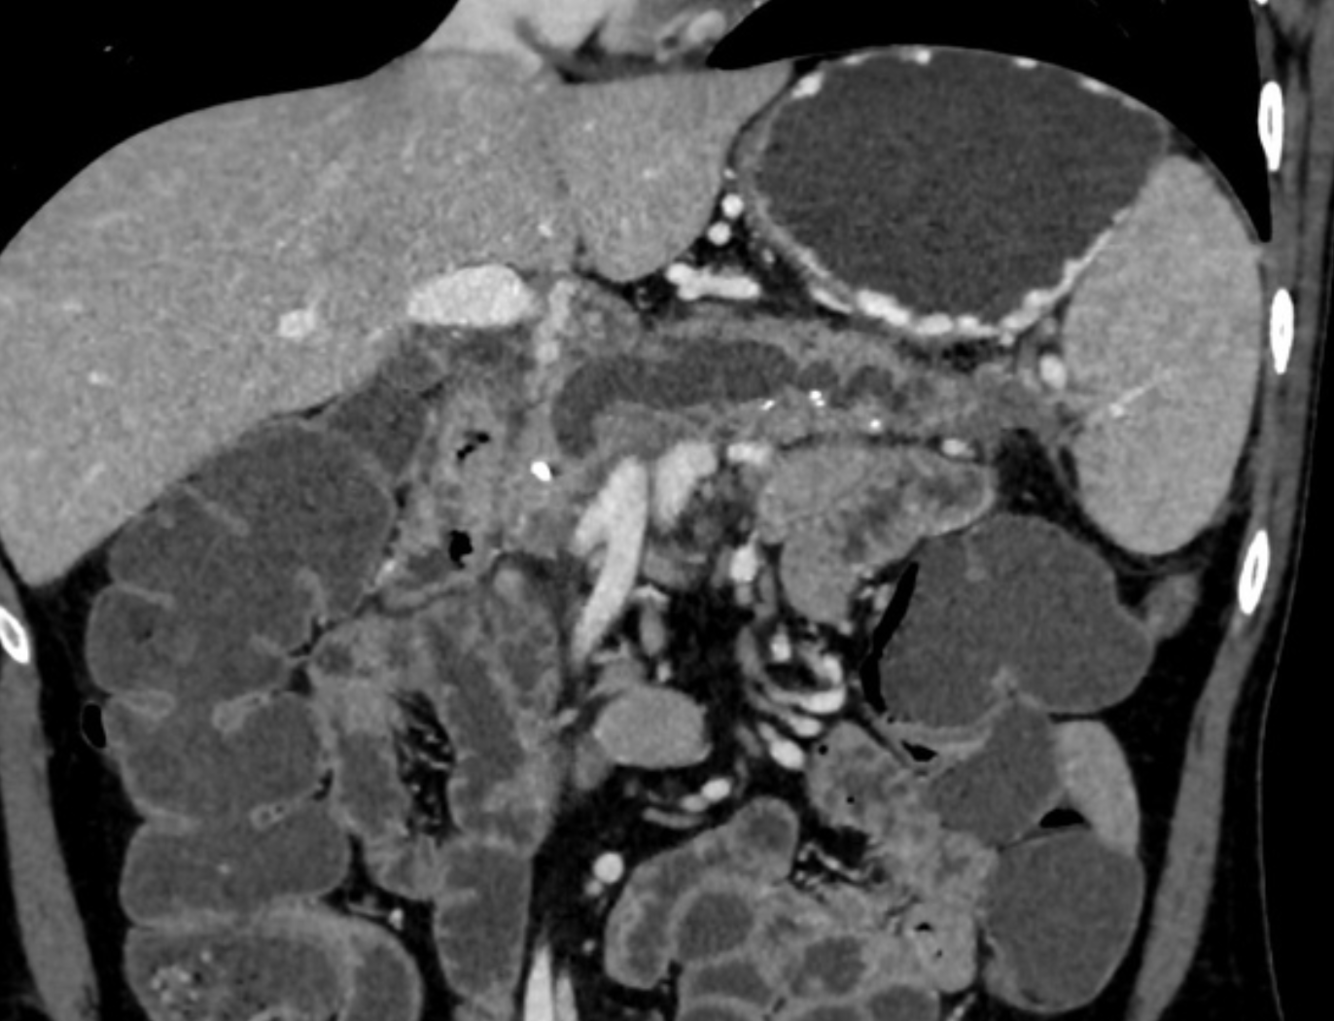

Single phase CT scan (multiphase scans not performed due to age of patient) demonstrates a diffusely enlarged pancreas with a “halo” like rim of hypoattenuating tissue which is smoothly marginated. Minimal peripancreatic fat stranding.

Associated splenic vein thrombosis, splenomegaly and cavernous transformation of the portal vein.